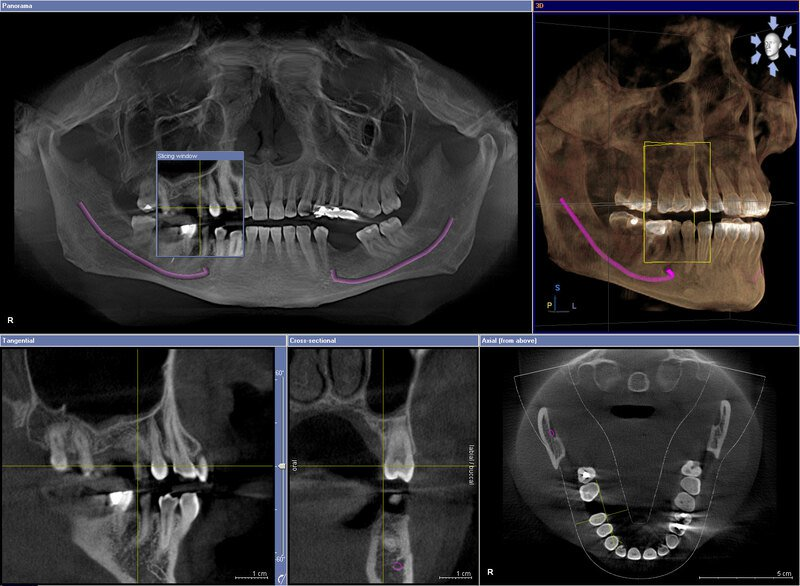

Cấy ghép implant: Cone Beam CT giúp chẩn đoán được tình trạng xương hàm, xác định kích thước và vị trí cấy trụ implant, ngoài ra, thông qua dựng ảnh 3D, bác sĩ có thể thực hiện cấy ghép implant mô phỏng trên phần mềm, từ đó giúp quá trình cắm ghép nhanh chóng và chính xác hơn.

Hỗ trợ trong chỉnh nha, niềng răng: Cone Beam CT cung cấp thông tin chính xác về tình trạng xương, vị trí của răng và chân răng từ đó có đưa ra kế hoạch điều trị chính xác. Nhổ răng khôn, răng ngầm: Hình ảnh ba chiều từ máy chụp sẽ cung cấp cho nha sĩ hình ảnh chiều thế mọc của răng khôn, biết được dây thần kinh nằm ở đâu, có bị răng khôn chèn vào không từ đó thực hiện nhổ răng một cách an toàn hơn. Các trường hợp nội nha phức tạp: Cone Beam CT giúp bác sĩ khảo sát được những thông tin mà phim quanh chóp thông thường không khảo sát được như số lượng ống tủy, độ cong ống tuỷ, tình trạng canxi hóa, tổn thương nứt chân răng… từ đó có phương pháp điều trị thích hợp nhất. Phát hiện các bệnh lý vùng hàm mặt: Khối u, rối loạn khớp thái dương hàm và bệnh xoang hàm Và bất thường không quan sát rõ trên các phương pháp chẩn đoán hình ảnh thông thường như phim x quang, phim panorama.

- Khả năng tái tạo hình ảnh 3D, hỗ trợ bác sĩ phân tích và lên kế hoạch điều trị trong cấy ghép implant, chỉnh nha,…